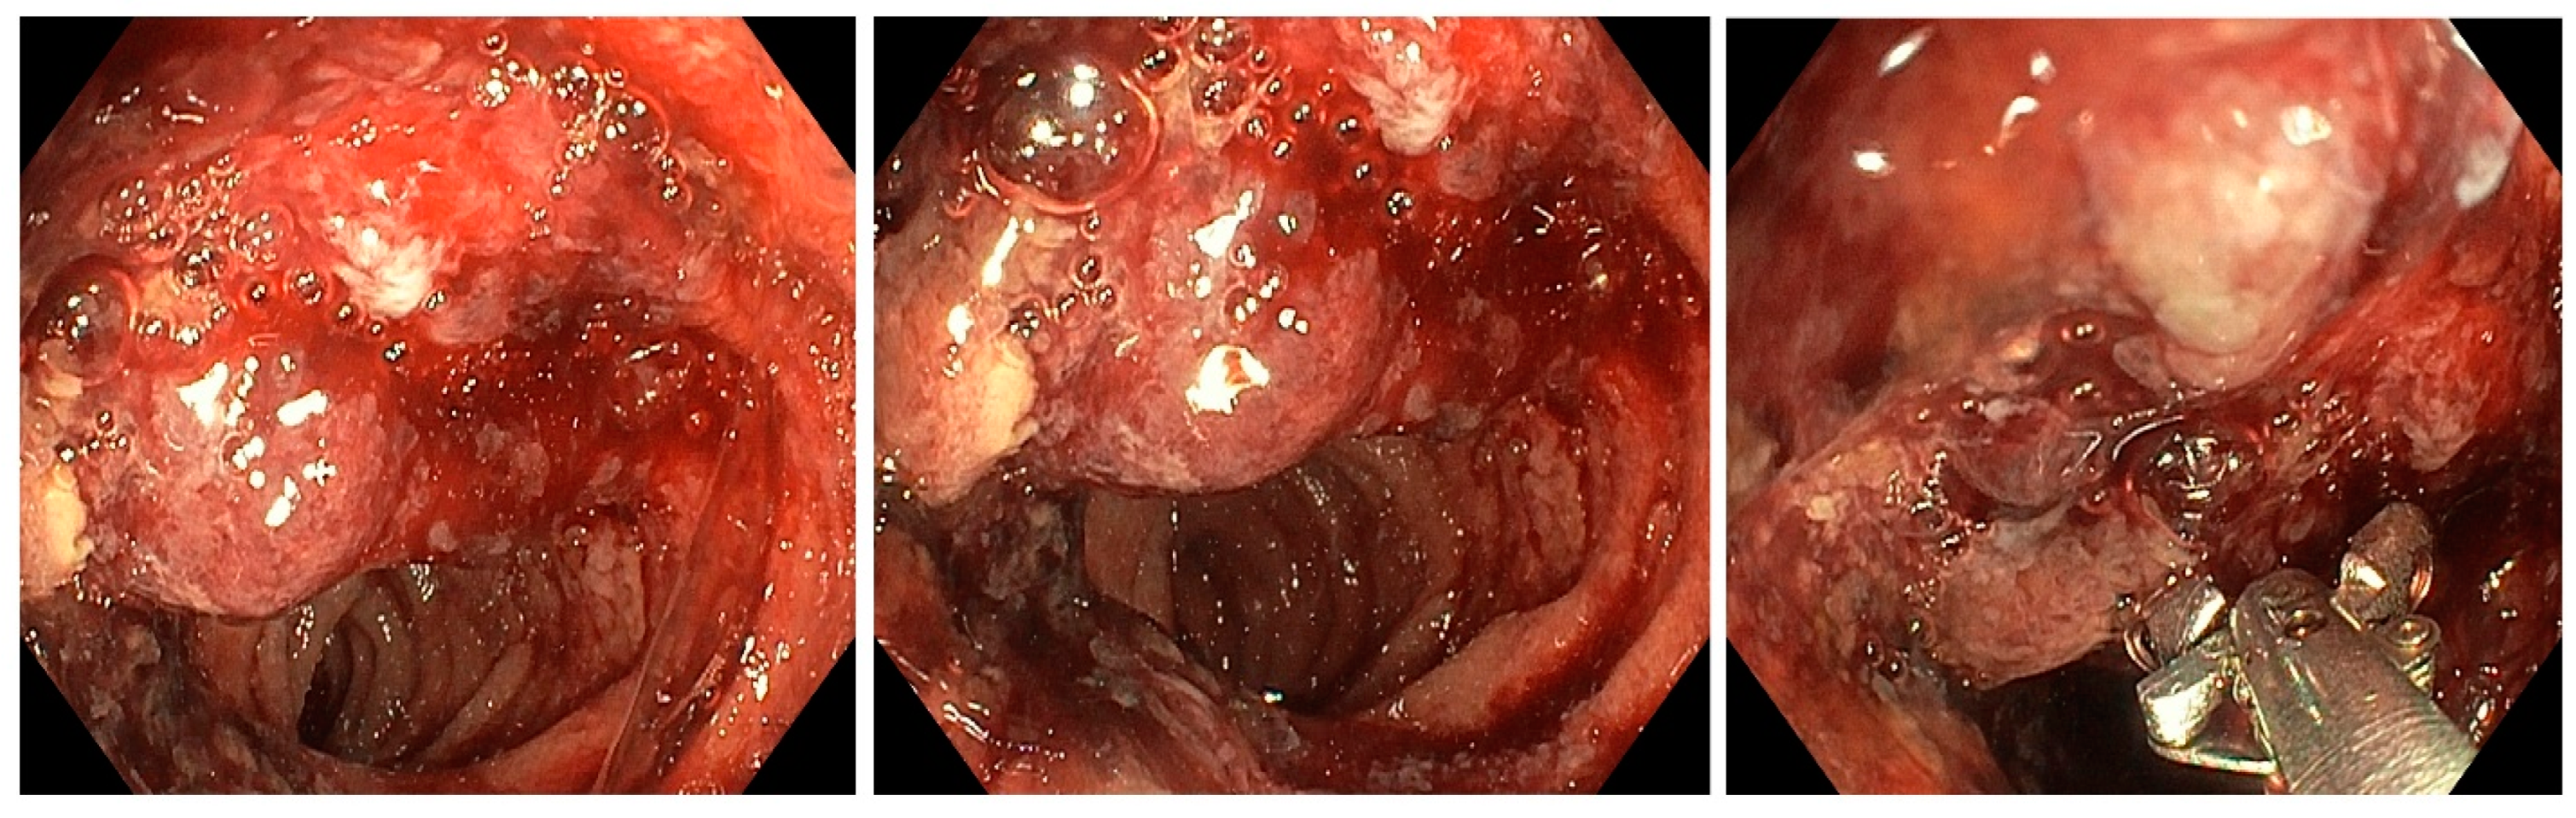

2.1. Motorized Power Spiral Enteroscopy